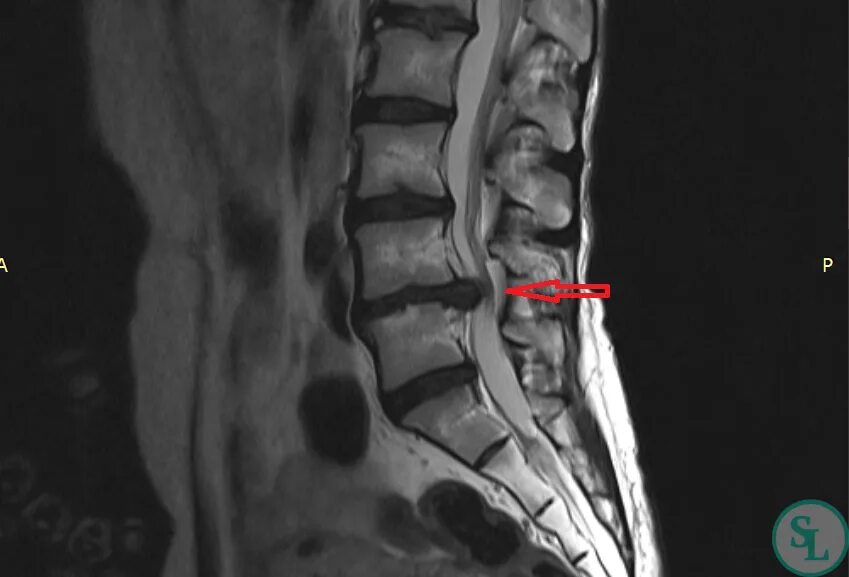

Протрузия l4 l5 лечение